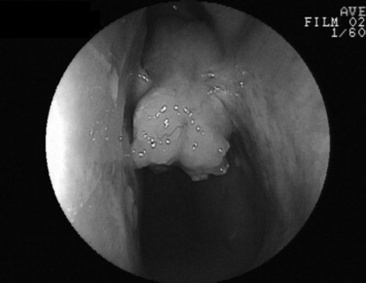

Fig. 31-25 Lateral thoracic radiographs from a foal with Histoplasma pneumonia.

Courtesy Carol Clark, Peterson and Smith Equine Hospital, Ocala, Fla.

Histoplasmosis is caused by the saprophytic, dimorphic fungus H. capsulatum, which is most prevalent in moist soil containing bird or bat waste. Yeast organisms are 2 to 4 μm in diameter, with a thin clear halo surrounding a round or crescent-shaped basophilic cytoplasm (Fig. 31-24). Histoplasmosis has been reported in less than 10 equine cases,330 and thus horses are considered to be relatively resistant to disease. H. capsulatum may occur in an enteric, pulmonary, or disseminated form.330H. capsulatum was identified in pulmonary granulomas in a horse dying of chronic Yersinia colitis372 and in another horse with intestinal salmonellosis.373 It has also been associated with abortions and severe granulomatous pneumonia in neonatal foals (Fig. 31-25) and a yearling.374 Successful treatment with amphotericin B was reported in a filly with pulmonary histoplasmosis diagnosed by cytologic identification of the organism on a tracheal wash smear and from a lung aspirate.330